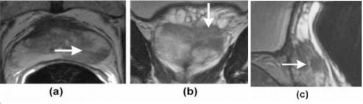

A special type of Magnetic Resonance Imaging (MRI) called multiparametric MRI (mpMRI) is used to plan, guide delivery, and confirm the effect of Focal Laser Ablation. Multiparametric MRI clearly characterizes a cancerous tumor within the prostate gland. It reveals the location, shape and extent of the tumor.

Once the target tumor is defined, the doctor can plan where to place the laser fiber in order to destroy the targeted area plus an extra safety margin. This planning includes the location and depth so the tip of the fiber is strategically placed to maximize the laser’s effect. Since the fiber is visible on MRI, the doctor knows that its placement is accurate.

The doctor can monitor the ablation as it occurs. When the laser is activated, the heat quickly expands with precise boundaries. Special MRI software called thermometry makes a temperature map of the prostate and the ablation. It shows the size and temperature of the laser-generated heat as it destroys the tumor and the safety margin. Thus, the doctor can avoid damage to nearby urinary and sexual structures, sparing normal prostate function.

When the ablation is complete, a final MRI scan is done to confirm that the targeted ablation matched the planned area. Also, multiparametric MRI can characterize the destroyed tissue, assuring there is no surviving cancer activity in the targeted area.